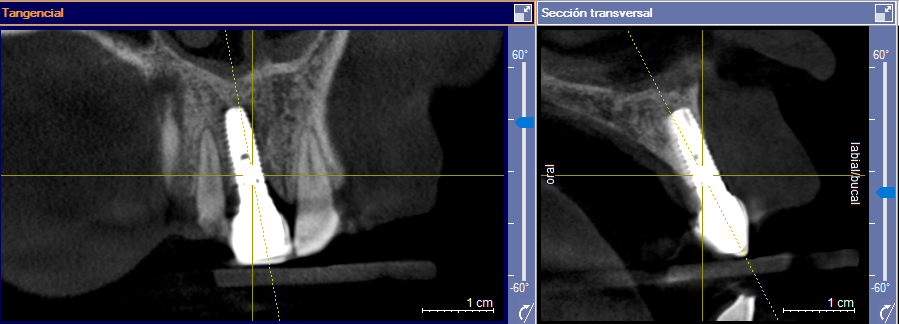

El implante 16 parece ser de una pieza con el pilar. El implante en 14 parece ser de una pieza con un cuello cerámico . Sabéis la marca . Microdent [...]